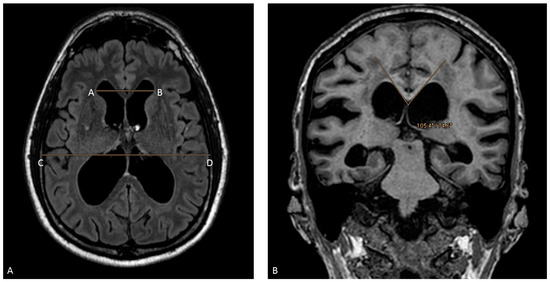

- Imaging characteristics of hydrocephalus with disproportionated enlargement of the ventricles in comparison to the outer subarachnoid spaces, whereby an Evans’ index >0.30 was indicative of iNPH on computed tomography (CT) or magnetic resonance (MR) imaging;

- Callosal angle of <90°;